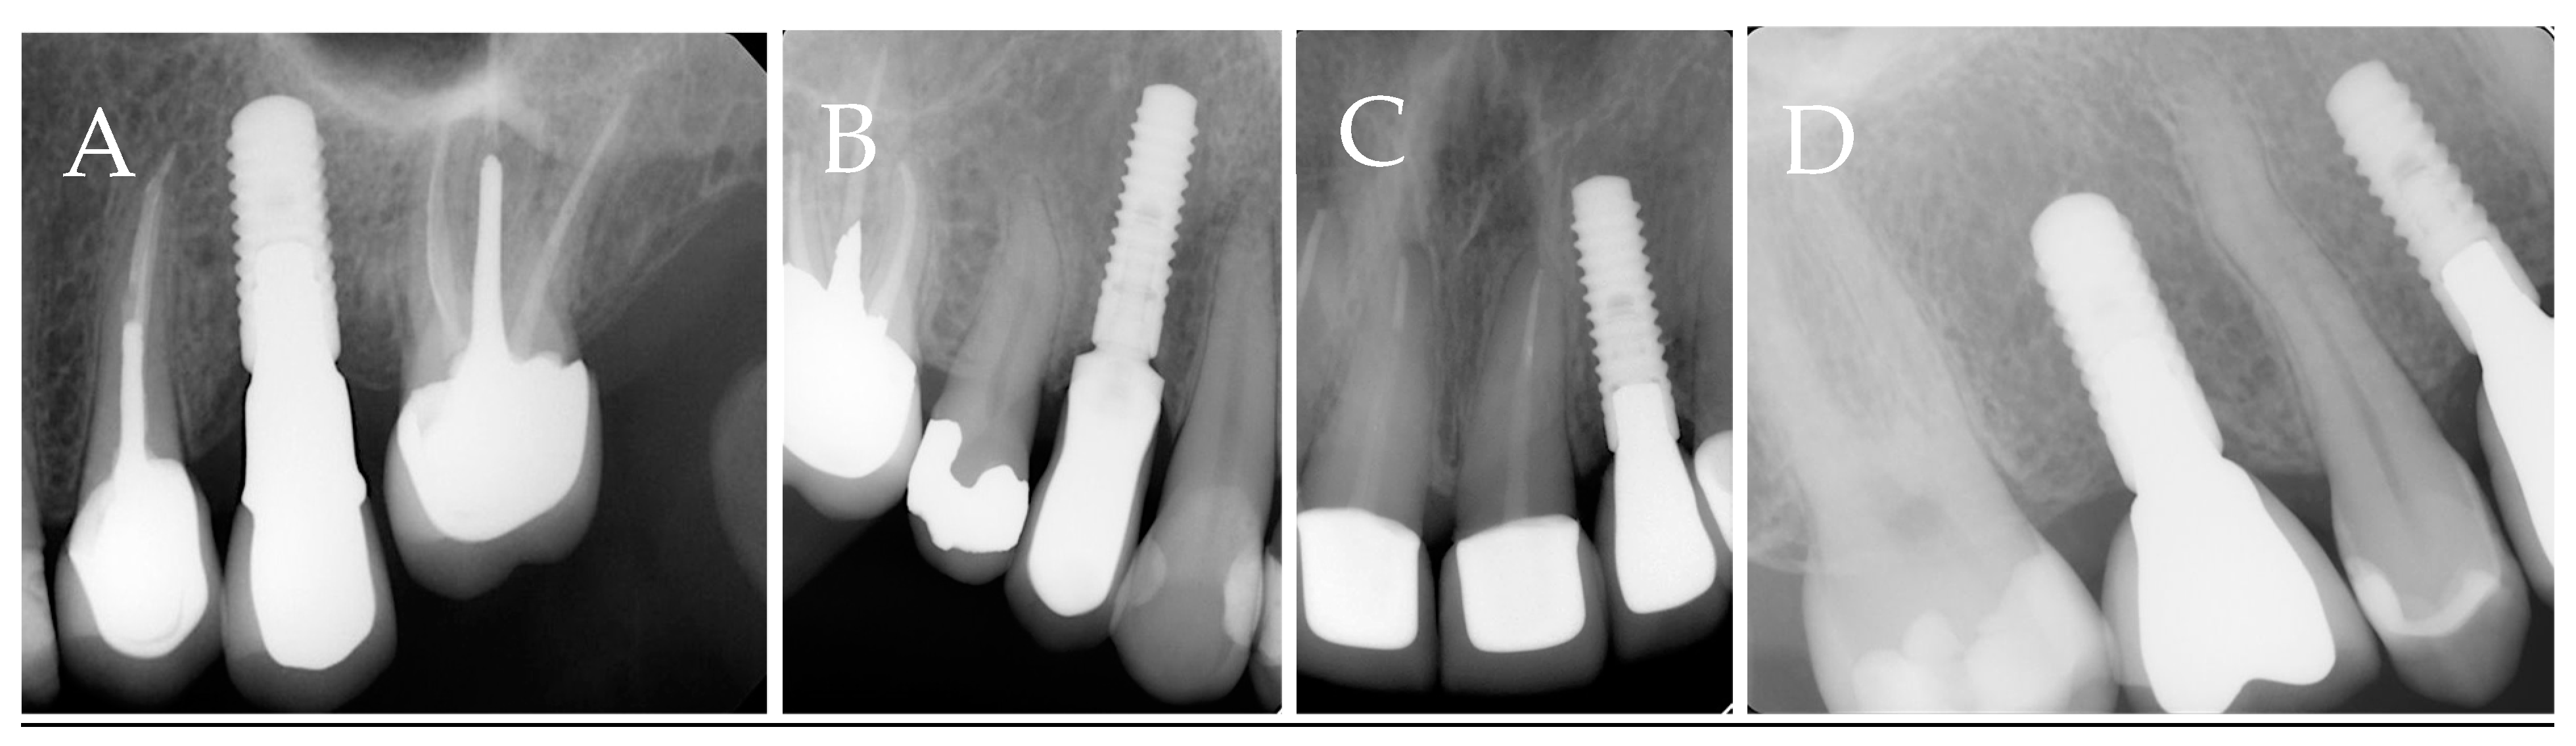

Categories A, B, and AB will be grouped into endodontic involvement (EI) groups. And category C will be considered the non-endodontic involvement (NEI) group. Data regarding the group distribution are shown in Figure 1. The radiographic representations of each study group are shown in Figure 2.

Figure 2. Radiographs representing different study groups. (A). Category A, implants placed next to endodontically involved teeth. (B). Category B, implants placed at a site with previous endodontic involvement within 6 months of extraction. (C). Category AB, implants that fulfill the criteria of groups A and B. (D). Category C, implants that are placed at a site with no previous endodontic involvement or a site with previous endodontic involvement that is allowed to heal for more than 6 months and next to vital teeth.